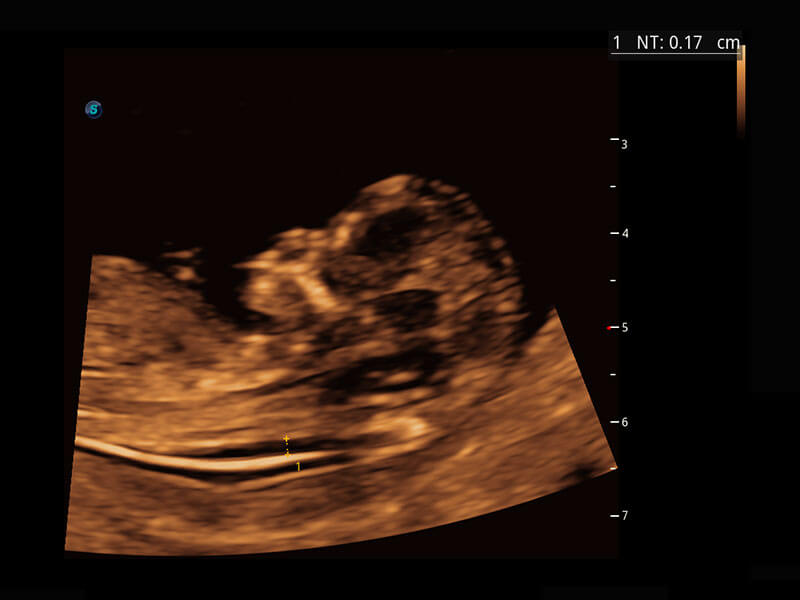

P60在胎兒早孕期超聲篩查中為您帶來優(yōu)異的圖像質(zhì)量。

早孕-胎心

高分辨率容積成像-早孕胎兒